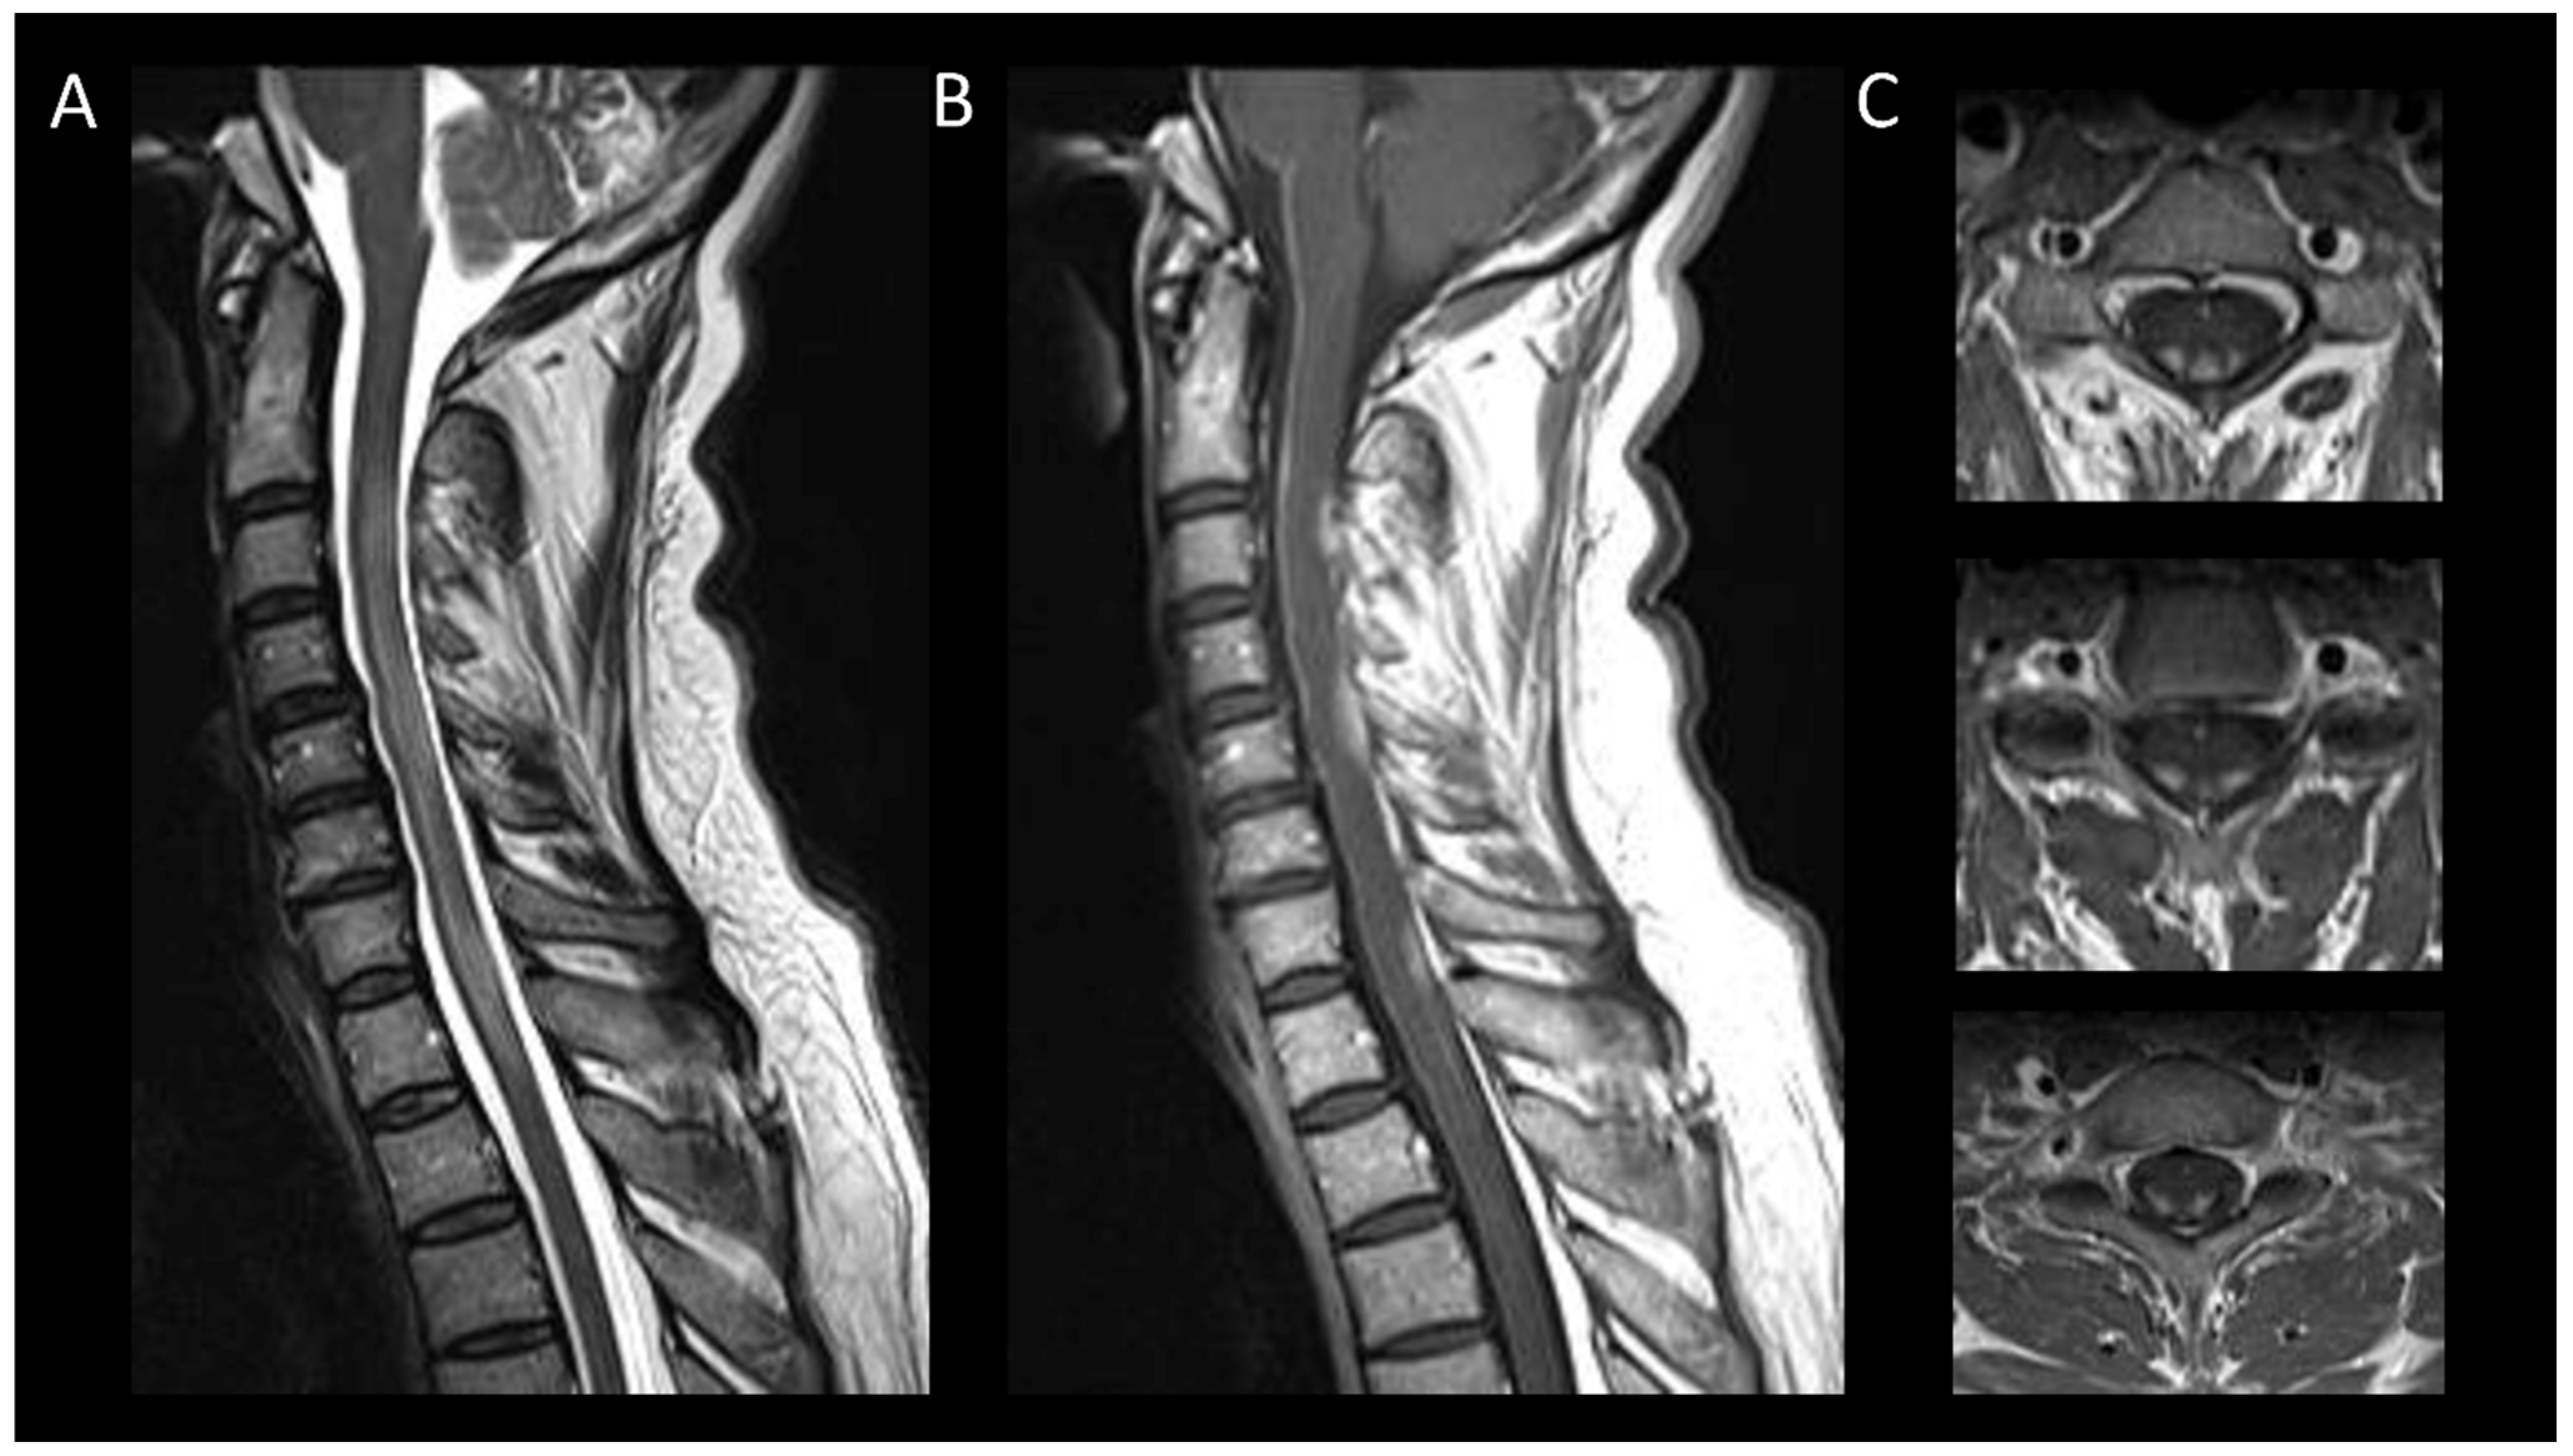

3.2. Degenerative Compressive Myelopathy

3.3. Vascular Myelopathies

3.3.1. Spinal Cord Infarction

3.3.2. Spinal Dural Arteriovenous Fistula